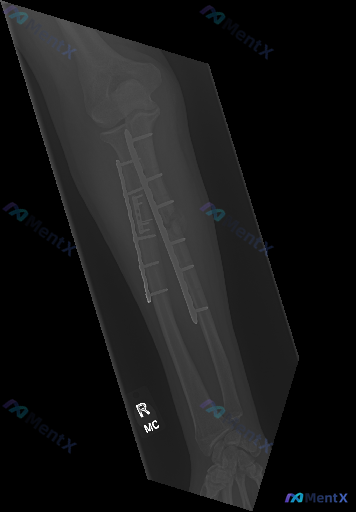

整理到一张左前臂正位X光片的读片资料: 基本背景:左前臂尺桡骨骨折术后复查 影像观察到的基础信息: - 尺、桡骨干均有金属接骨板+多枚螺钉固定 - 骨折断端对位对线尚可,未见明确内固定松动、断裂或移位 - 骨折区域可见初步骨痂生长影 - 腕关节、可见的部分肘关节结构尚完整,关节间隙无明显狭窄/增宽...